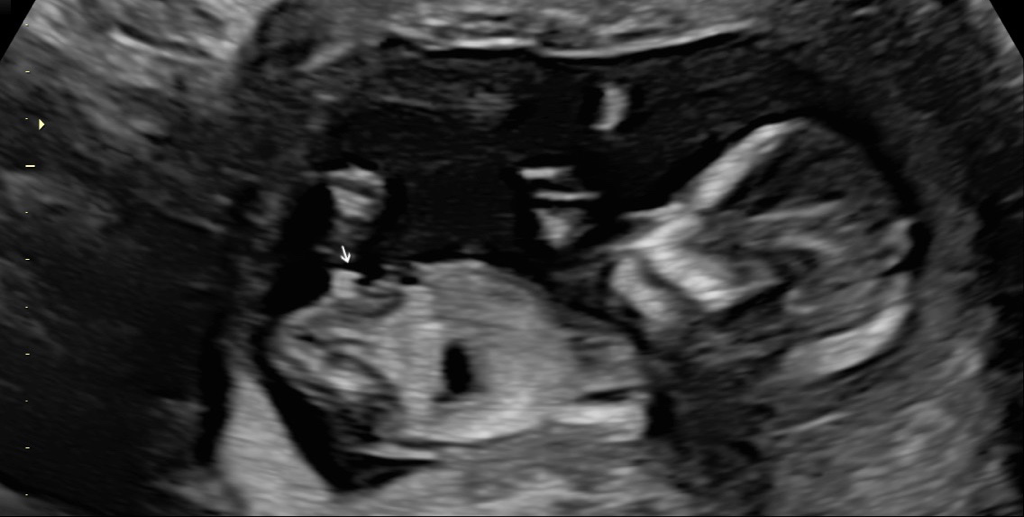

請問這樣確定是男寶了嗎?醫生說12週六七成看起來是男寶,但是也有可能是臍帶,因為大寶是兒子好想要來個女兒,凸起物很明顯這樣有可能翻盤嗎